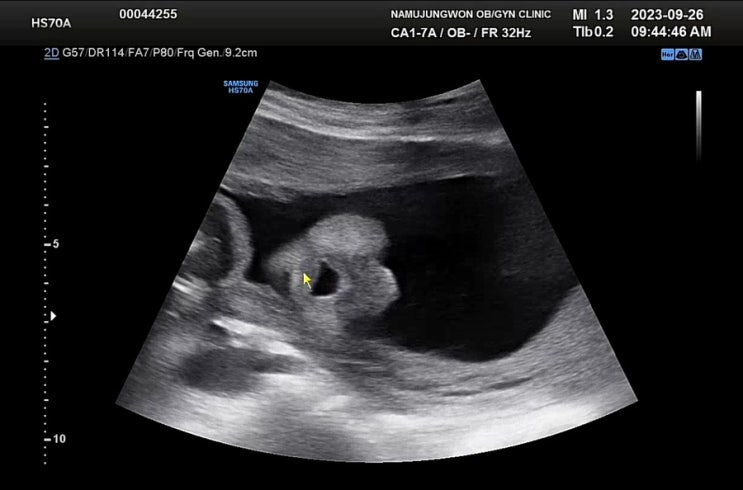

자궁경부무력증 임신 24주차 우동이 기록 정밀초음파 실패

첫째인 우주가 자궁경부무력증으로 아주 큰일날뻔 했던 이력이 있어서 둘째 우동이 임신 후에는 바로 동탄...